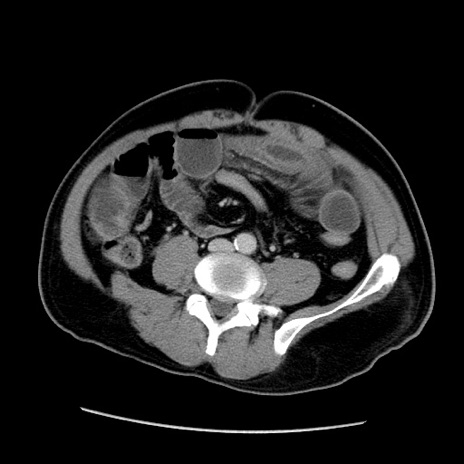

症例22(横断像)

【症例】50歳代男性

【主訴】腹痛

【現病歴】AVMからの被殻出血のため回復期リハ病棟入院中。 本日午後3時頃急に下腹部痛が出現した。

【既往歴】AVM、被殻出血、虫垂炎、高血圧

【身体所見】意識晴明、左半身不全麻痺、会話の理解は良好、36.5°C、腹部:膨隆、全体に板状硬、下腹部正中に圧痛点あり、反跳痛-、筋性防御不明、右下腹部にope scar

【データ】WBC 9400、CRP 0.06